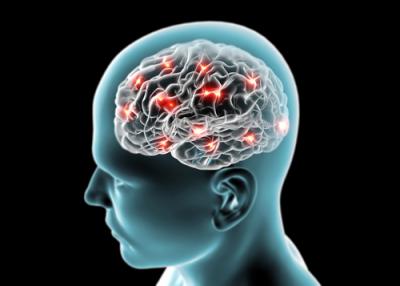

כך נזהה שבץ מוחי

בישראל לוקים מידי שנה כ-15,000 איש בשבץ מוחי. שבץ מוחי, הנקרא גם אירוע מוחי, הנו מצב רפואי חמור, מסכן חיים, הדורש טיפול חירום מיידי. השבץ יכול לגרום לנזק מוחי מתמשך, נכות לטווח ארוך או אפילו מוות. יאן גרינברג, מנהל תחום הטבע ב""טלפארמה"" בית המרקחת המקוון, מסביר מהו אירוע מוחי, אילו סוגים של שבץ קיימים, מהם גורמי הסיכון, תסמיני אירוע מוחי ומהי בדיקת נטייה לשבץ.

שבץ מוחי מוגדר כחוסר תפקודי נוירולוגי באחד מאזורי הגוף, על רקע פגיעה בזרימת הדם למוח. הנזק הנגרם באירוע מוחי גורם לפגיעה ברקמות המוח אשר הפגיעה הנפוצה היא חסר בהספקת חמצן. ללא חמצן, תאי המוח מתחילים להתנוון ולמות אחרי כמה דקות. במקביל, גם דימום פתאומי, היוצר לחץ על רקמות המוח, יכול לגרום נזק בלתי הפיך לתאים.

תסמיני שבץ הם רבים ויכולים להופיע כחולשה פתאומית, שיתוק או חוסר תחושה בפנים, בזרועות, ברגליים, קושי בדיבור או בהבנת הדיבור, הפרעות ראייה.